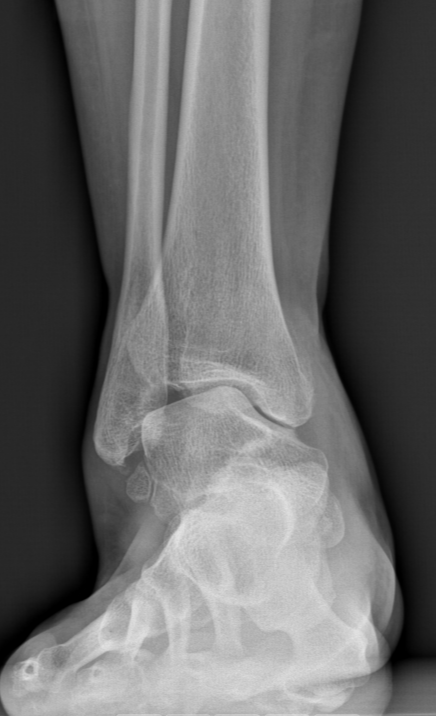

术前踝关节正位X线

术前后足力线X线